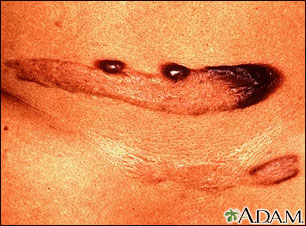

A keloid is a growth of extra scar tissue. It occurs where the skin has healed after an injury.

A keloid may be:

- Flesh-colored, red, or pink

- Located over the site of a wound or injury

- Lumpy or ridged

- Tender and itchy

- Irritated from friction such as rubbing on clothing

A keloid will tan darker than the skin around it if exposed to the sun during the first year after it forms. The darker color may not go away.